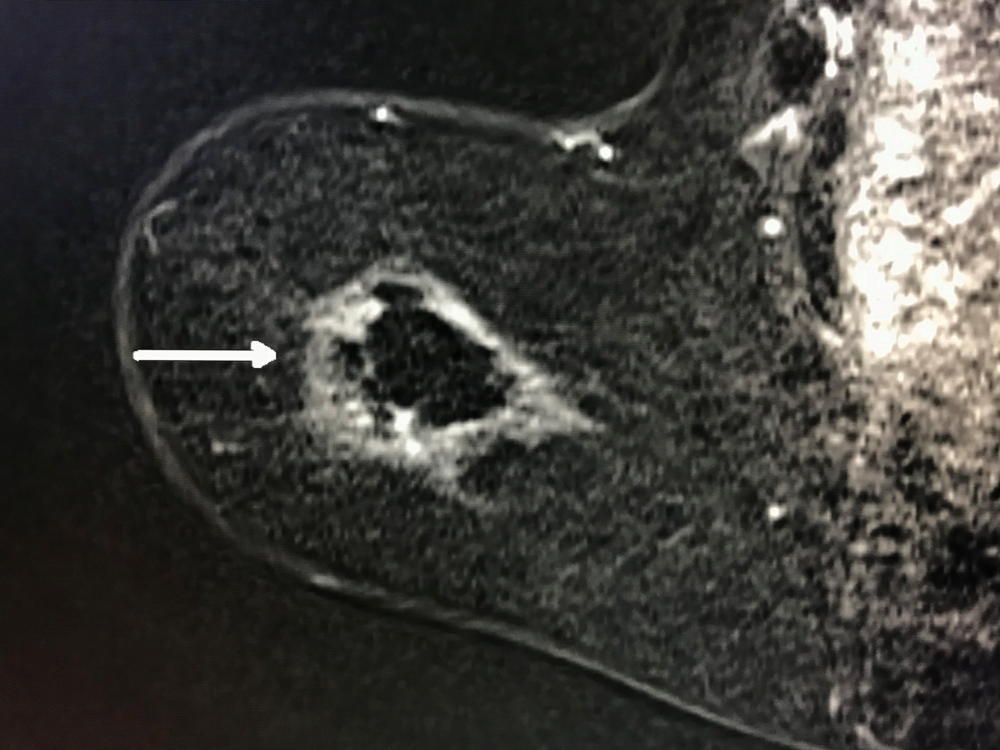

Figure 4. MRI post ablation shows white outline of ablation zone referred to as "cryohalo" with normal dark breast tissue centrally and no evidence of residual cancer (arrow).

High-res (TIF) version